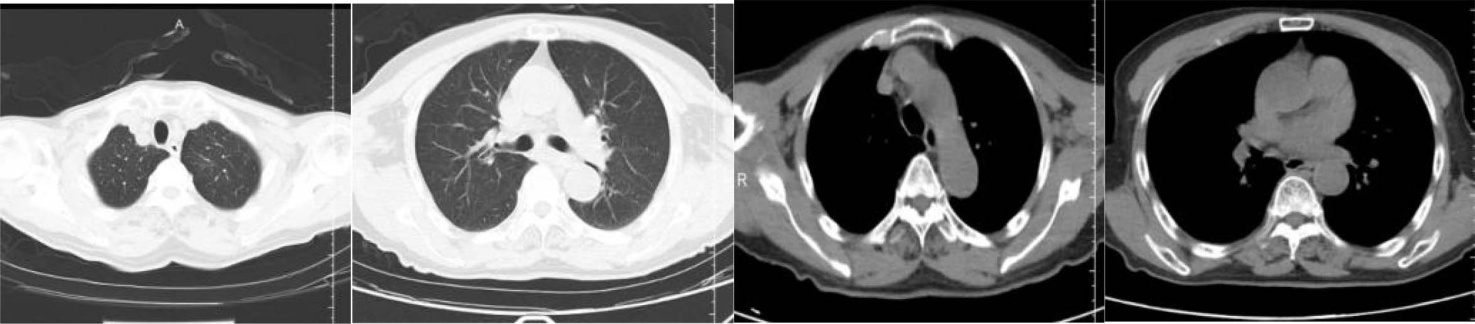

胸部CT:双肺渗出性改变。双侧胸腔少量积液。支气管炎表现。纵隔淋巴结肿大(图5)。

Figure 5. Chest CT results

5. 胸部CT结果

胸部CT:左肺下叶后基底段气管不通并肺内高密度灶,考虑占位;纵隔多发肿大淋巴结,转移可能;双肺炎症,左前胸壁皮下结节,建议复查。(医院CT室)。

a) 胸部CT:诊断意见:左肺下叶占位,考虑肺Ca;结合临床。纵隔、左肺门淋巴结。胸壁软组织结节,考虑转移(图9)。

Figure 9. Results of chest CT examination

9. 胸部CT检查结果

影像学检查在多抗体阳性AE中常缺乏特异性。本例患者头颅MRI仅显示多发性脑梗死和脑白质脱髓鞘,未出现抗NMDAR脑炎常见的颞叶内侧高信号或抗GABABR脑炎的单侧/双侧颞叶异常[9]。这种“影像学阴性”表现约见于20%的多抗体阳性病例,可能与抗体对神经元功能的可逆性干扰而非结构性破坏有关[10]。胸部CT提示的左肺下叶占位及纵隔淋巴结肿大,结合神经元特异性烯醇化酶(94.24 ng/mL)和胃泌素释放前肽(>5000.00 pg/ml)的显著升高,高度提示SCLC的可能,而胸壁肿物病理检出的鳞状上皮细胞进一步支持恶性肿瘤的诊断[11]